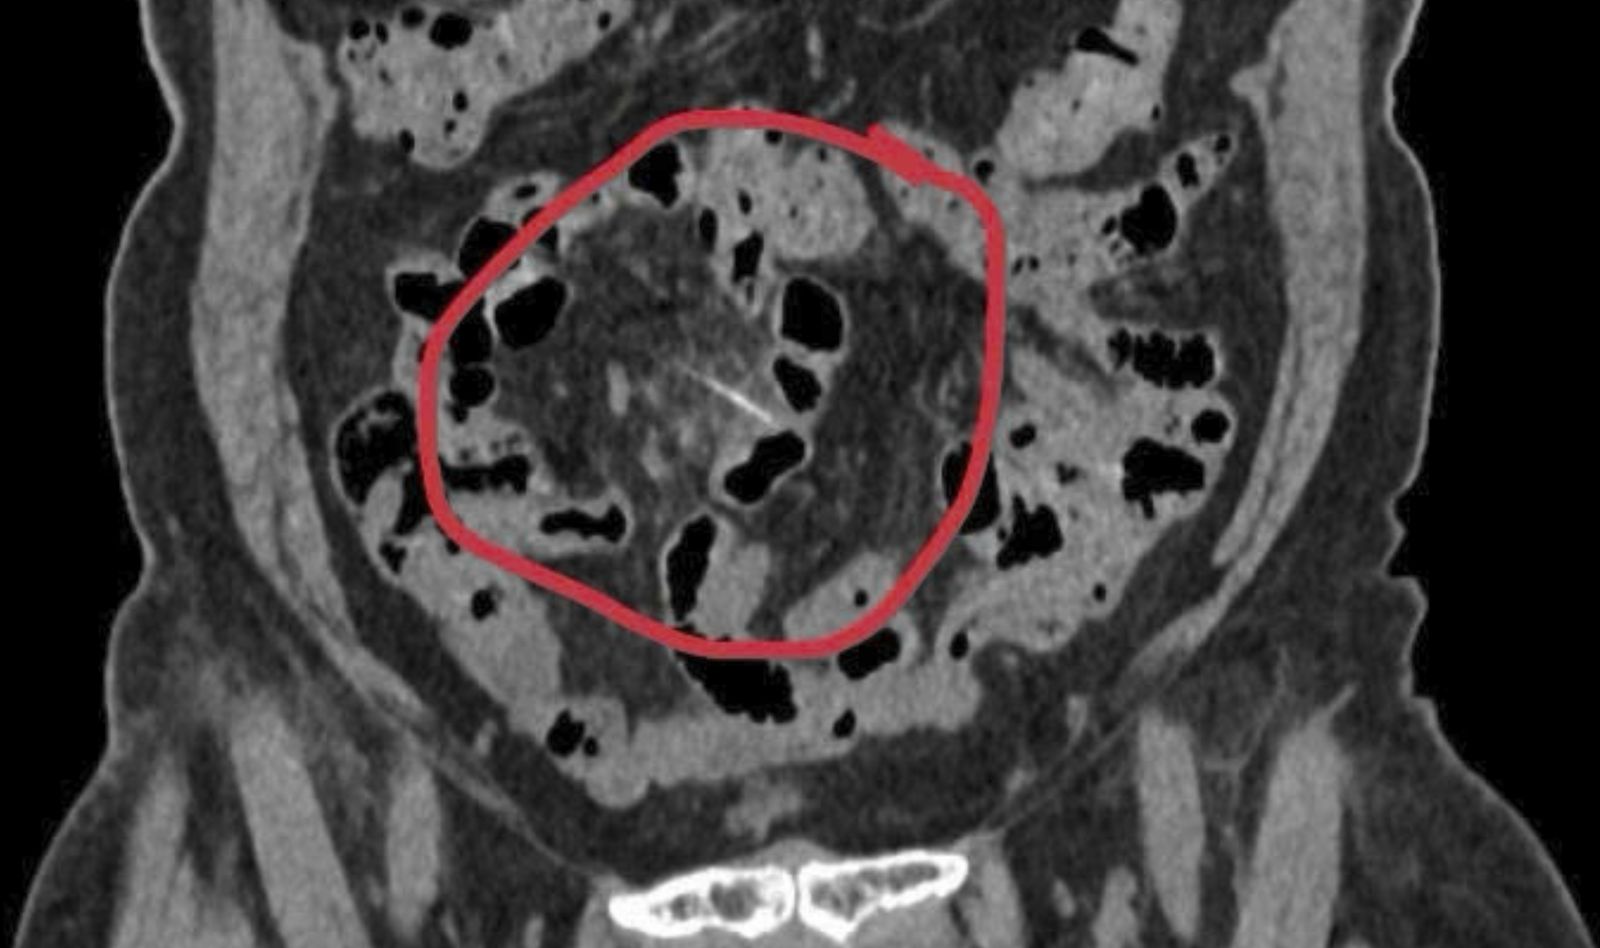

Chụp cắt lớp vi tính phát hiện dị vật dài khoảng 3cm nằm trong đoạn cuối ruột non – nghi là xương cá trong ruột cô Xuyến.

Trước đó, người bệnh Phan Thị Xuyến nhập viện khoa Cấp cứu, Bệnh viện Đa khoa Trung ương Quảng Nam trong tình trạng đau bụng âm ỉ vùng rốn lệch phải, cơn đau tăng dần. Qua thăm khám và chẩn đoán hình ảnh, các bác sĩ khoa Ngoại tổng hợp phát hiện dị vật dài khoảng 3cm nằm trong đoạn cuối ruột non – nghi là xương cá.